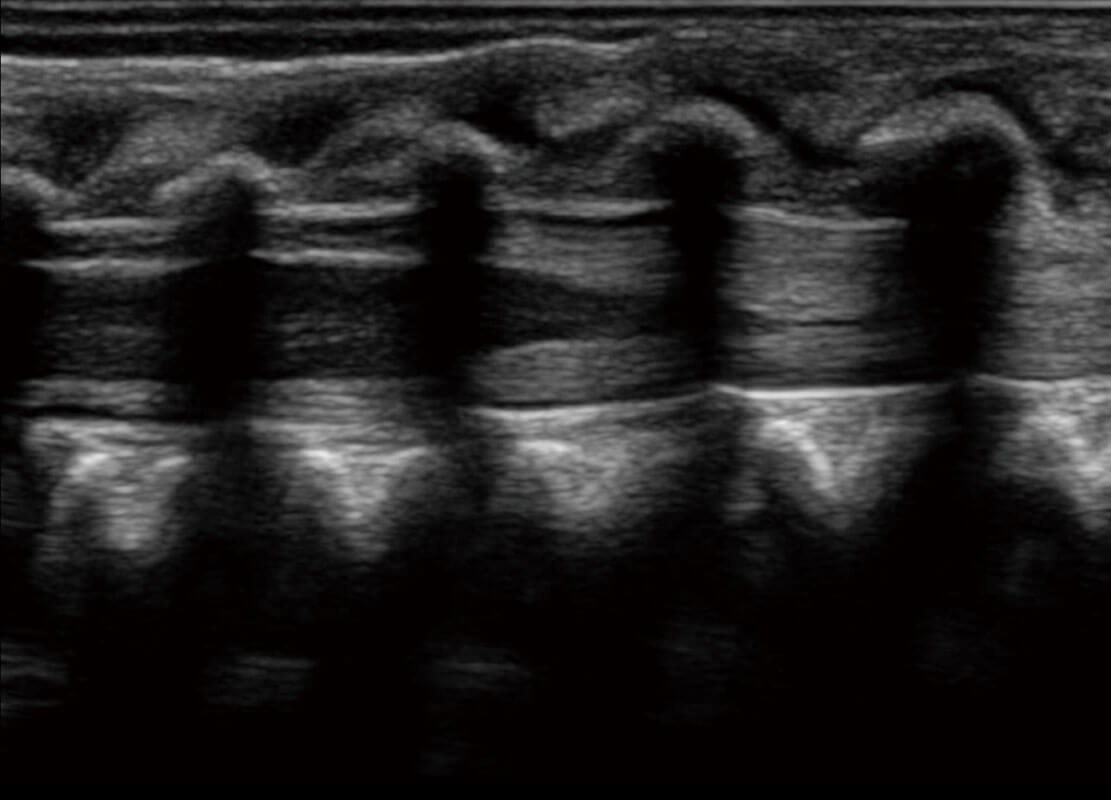

四腔切面